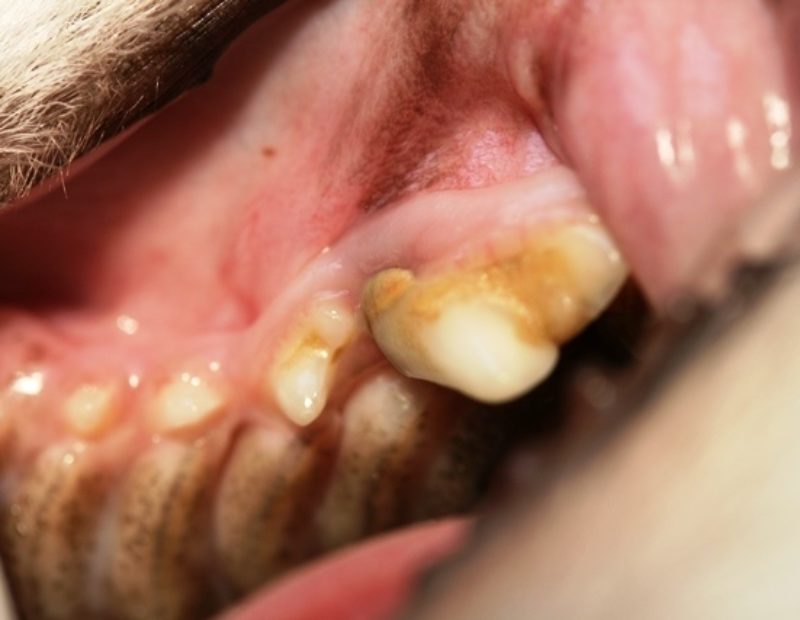

Der Chihuahua-Rüde ist sozusagen unser Zahnvorzeigepatient, und wir freuen uns jedes Jahr über seine topgepflegten Zähne, doch leider kam es anders als erwartet. Im Rahmen der gründlichen Untersuchung, die zu jeder Impfung dazugehören sollte, durfte uns Pico seine Zähne zeigen. Schnell fielen Rötung, Schwellung und Rückbildung des Zahnfleisches  im Bereich der vorderen Wurzel des Reißzahnes im linken Oberkiefer auf (Bild 1). Außerdem wies dieser Zahn im Vergleich zur Gegenseite eine deutliche Zahnsteinbildung auf. Die Parodontalsonde, ein spezielles Instrument mit einer Skalierung zum Ausmessen von Zahnfleischtaschen, brachte das Ausmaß des Schadens an das Licht. Die Sonde ließ sich fast einen Zentimeter tief in das Zahnfach einführen (Bild 2+3).